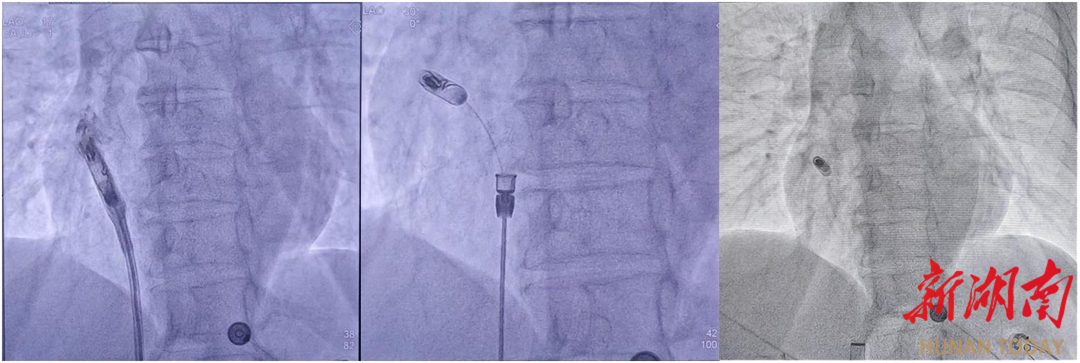

手术当天,该团队邓策、彭林林携手合作,通过患者右侧股静脉入路将仅有传统起搏器十分之一大小的新型心房无导线起搏器精准输送至右心,牢固地锚定在右心耳基底部上。手术过程顺利,起搏器工作正常,患者立即恢复正常心跳术后10小时后即可正常下床活动。

而患者向某,则因阵发性房颤入院,拟行房颤射频消融术。住院期间了解到心血管内科引进了脉冲电场消融术,可快速实现肺静脉电隔离,避免传统消融易引发的心房食管瘘、膈神经损伤等并发症,且手术时间短、创伤小,于是果断选择房颤脉冲电场消融。手术当天,该团队利用脉冲电场消融系统高效完成手术,患者术后6小时即下床正常活动,无任何不适。